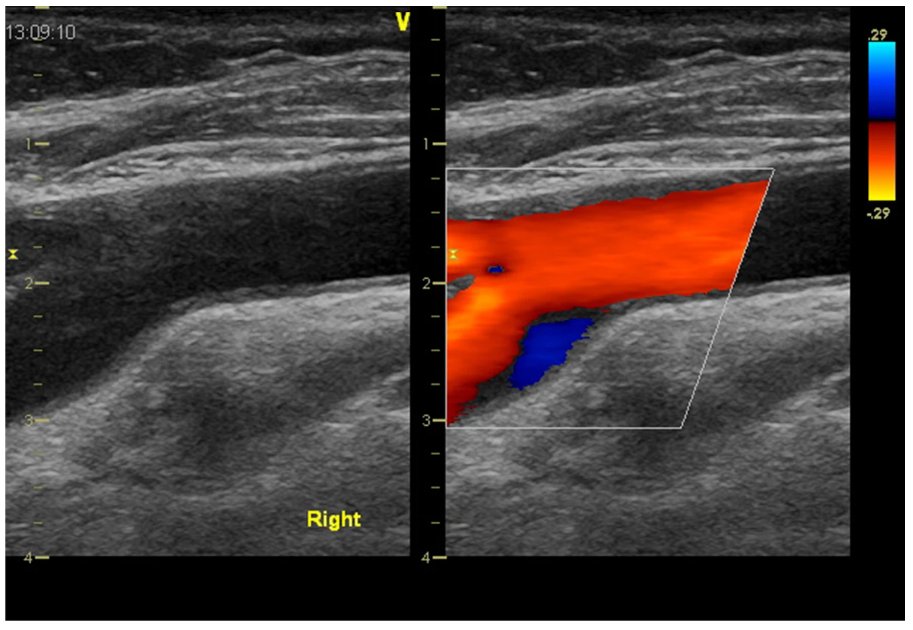

在直动脉段中,血流呈层流状,WSS 值在生理上保持在 10–50 dyne/cm2 的狭窄范围内。当血流需求增加时,例如在步行、慢跑等过程中,下肢的外周动脉阻力(小动脉张力)降低,而流速和容量增加。速度的提高意味着更高的 WSS。这被ECs检测到,并释放更多的一氧化氮以扩大供血动脉的直径,并使WSS正常化。然而,这种理想的机制在具有相对固定几何形状的动脉段中是无法实现的,例如在分叉的外壁(图2)或沿主动脉弓的内壁,其中血流比沿外壁慢。事实上,这些部位最常受到动脉粥样硬化的影响。内皮细胞倾向于与壁剪切应力对齐:壁剪切应力越高,细胞越细长,反之亦然。在狭窄的动脉段中,内皮细胞在分离区失去其细长的形状(图1)。颈内动脉最近端具有高度神经支配的扩张,称为颈动脉窦,也是斑块的常见部位。在颈动脉窦中,动脉内径突然变宽,无法流动,出现所谓的流动逆转模式,并可通过双多普勒超声显示(图2),甚至可以定量。

图2 颈动脉分叉时血流逆转。

颈动脉分叉纵切面在B模式(左)和彩色多普勒图(右)的图像。颈内动脉从扩张的部分(球状或窦)开始。在收缩期,直线段的血流加速,但在颈动脉窦(蓝色区域)发生血流逆转。颈动脉窦中的低振荡WSS是动脉粥样硬化斑块早期发展的原因。